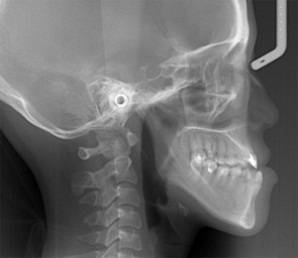

放射检查:一般包括X线头影测量片、曲面体层片和CBCT(锥束CT)。有时还包括其他放射检查,比如螺旋CT等。通过放射检查,医生可以看到骨骼及牙齿的形态、位置及发育状况,以及是否有牙体、根尖周、牙周疾病等,从而评估是否需要正畸治疗、进行何种治疗。

头影测量片(上)、曲面体层片(中)和锥束CT(下)